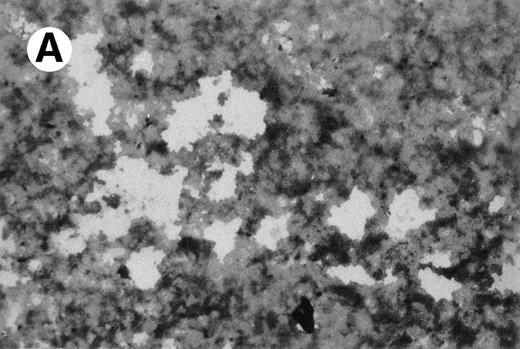

Primary mononucleated interphase cells were maintained in liquid culture supplemented with IL-3 for 8 weeks, during which time cell growth stabilized with a doubling time of 4 to 7 days. A cell aliquot was then transferred to semisolid cultures supplemented with IL-3 (5 ng/mL). Individual cells were obtained by hand-picking from semisolid cultures and were moved again to suspension culture. One cell line, designated UG3, grew as a single-cell suspension with a doubling time of 60 to 70 hours in the presence of IL-3. UG3 cells were round with basophilic cytoplasm that contained azurophilic granules and had soy-bean like nuclei with a few nucleoli (Fig 1).

Morphology of UG3 cultured in the presence of IL-3 (5 ng/mL). May-Grünwald-Giemsa staining. Original magnification, 300-fold.

Specific staining showed that UG3 cells cultured with IL-3 were 98% positive for αNB esterase, 13% double-positive for αNB and NAC esterase (Fig 5A), and negative for peroxidase and NAP (data not shown). UG3 cells cultured with GM-CSF showed increased αNB activity and decreased NAC activity (Fig 5B) as compared with UG3 cells maintained in the presence of IL-3. A few of the cells cultured in the presence of GM-CSF were of macrophage-like appearance, having wide and irregular cytoplasm, and grew adherently. In contrast, about 45% of UG3 that were cultured in the presence of M-CSF grew adherently. Nonadherent cells obtained from M-CSF–supplemented culture showed the same morphological characteristics as UG3 cells that had been maintained in the presence of IL-3, but stained 100% positive for αNB and negative for NAC esterase (Fig 5C). Adherent cells obtained from cultures maintained in the presence of M-CSF showed macrophage-like morphology with widely spread cytoplasm containing vacuoles (Fig6A) and also displayed strong positivity for αNB esterase (Fig 6B). In contrast, UG3 cells cultured in the presence of G-CSF featured a slightly irregular cytoplasm, contained granules, and showed increase of NAC esterase positivity (Fig 5D). These cells were 4% positive for peroxidase (Fig 7A) and 6% for NAP (Fig7B). Some UG3 cells maintained in the presence of G-CSF had a segmented nucleus (Fig 7A).

Double staining for α-naphthyl butyrate esterase and naphthol AS-D chloracetate esterase of UG3 cells cultured with IL-3 (5 ng/mL; A), GM-CSF (1 ng/mL; B), M-CSF (100 ng/mL; C), and G-CSF (10 ng/mL; D) for 2 weeks. Original magnification, 200-fold. Histochemical analyses were performed using samples taken from four independent cell cultures.